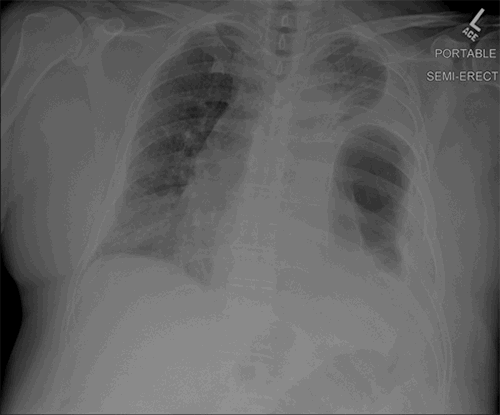

The postoperative course was relatively uncomplicated, and the patient was extubated on the third postoperative day after initially failing two spontaneous breathing trials. He was continued on nebulizer treatments and antibiotics. No specific antitussive medication was administered. A postoperative chest radiograph is shown in Figure 3. A chest CT performed two years postoperatively showed an intact repair (Figure 4).

Figure 4. Contrast-enhanced CT of the chest two years postoperatively showing an intact left diaphragmatic repair